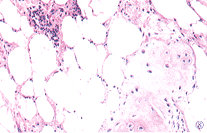

(2)組織形態:腫瘤由乳腺上皮性成分和間葉性成分兩者以不同的數量混合而成。根據上皮性成分和間葉性成分所占比例的多少,將本瘤分成3種類型:以上皮成分為主,稱為腺性錯構瘤(glandularhamartoma);以纖維組織占優勢者,稱為錯構瘤(fibroushamartoma);以脂肪組織占優勢者,稱為腺脂肪瘤(glandularpimeloma)。這是本病具有特色的一種徵象,瘤體內的腺體成分尚保持著分泌乳汁的功能。